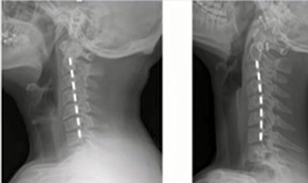

我们都知道脊柱在正常情况下,一共有4个生理弯曲,它们都有自己存在的意义与价值。其中颈曲是脊柱最上端的生理弯曲,是维持颈椎生理功能、稳定头部的基础。正常的颈椎生理曲度有一定缓冲压力的作用,在保护脊髓、神经根和血管上有着重要意义。正常的颈椎有一个向前的生理弧度,当颈曲弧度减小、消失时称为颈椎曲度变直,甚至反弓。